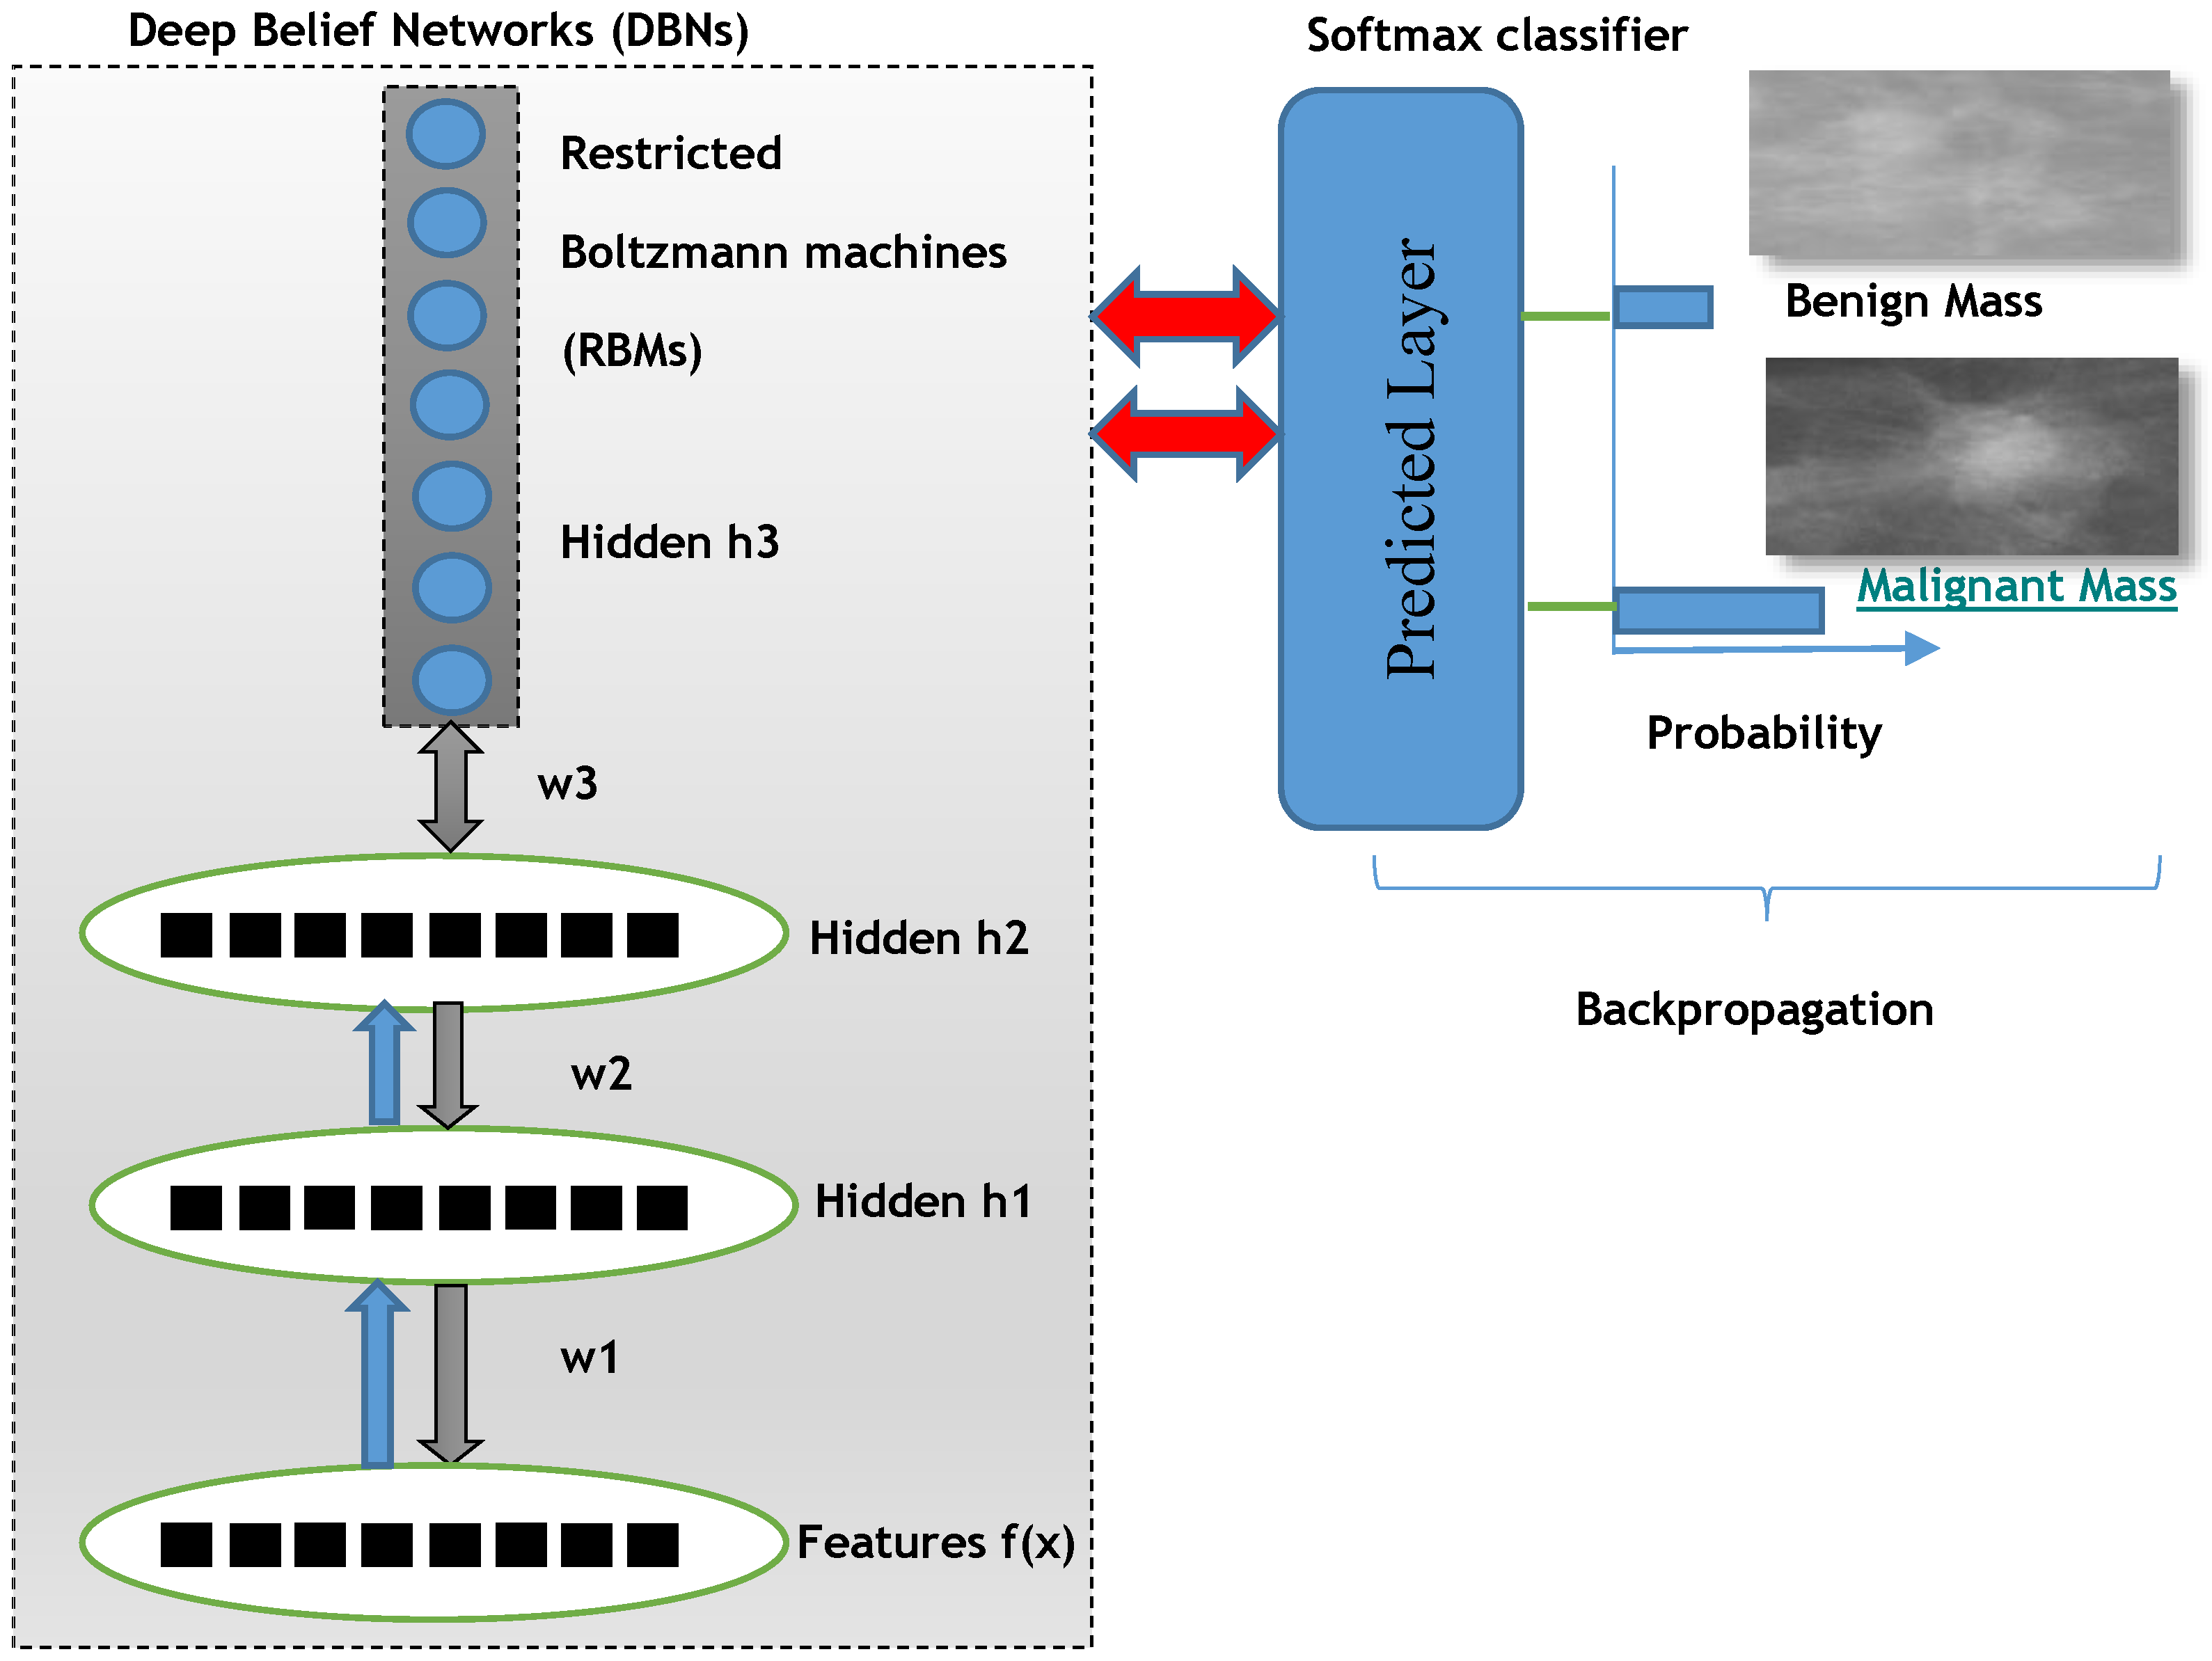

For deep learning DL-NN algorithms, the three layers from deep belief nets (DBNs) are employed along with a backpropagation optimization step. The DBNs are learned one layer at a time by learning the features that creates the bases for the next layer and so on. There is also fine-tuning step to improve the classification performance of the whole neural network model. This fine-tuning step is applied by using back-propagation error derivate and the final classification decision is performed by adding a softmax linear regression model.

The training of DBNs with RBMs started by using an unsupervised greedy layer-wise approach on the extracted invariant features. The first layer is visual that is defined as input of features. This unsupervised visible layer is used to construct the second layer by providing training examples as P(|). Afterwards, the second layer is trained as an RBM by using mean activation function of the training example. This step is iterated for desired number of layers by doing propagation upward the mean values of activation function.

The overall proposed deep learning architecture of DeepCAD system is depicted in

Figure 3 to predict benign and malignant masses.